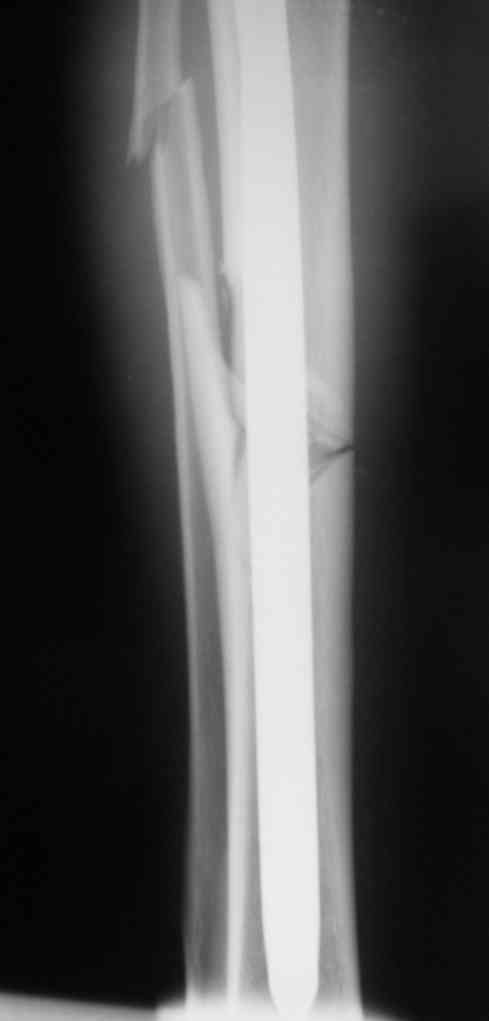

Дорогой Александр. Имею скромный опыт использования системы Fixion при

переломах плеча, бедра и тибии. Всего 18 наблюдений с сентября 2007

г.Результаты отличные. Гвоздь индивидуален для каждого медулярного

канала. Легко имплантируется как в узкий, так и в деформированный

канал. Это позволяет применять метод интрамедулярного остеосинтеза без

ненужных потерь времени операции, флюороскопии и реально снижает

крвопотерю и операционный риск. Удаление происходит без проблем.

Особенно интересны больные с ипсилатеральными переломами бедра и голени.

В отношении ранней нагрузки при спиральных переломах лучше не

торопиться. По данному случаю необходимо достигнуть исчезновения щели

между штифтом и внутреним кортексом по Rg. А так картинка прекрасная -

и длина сегмента и репозиция. Можно поздравить, коллега!